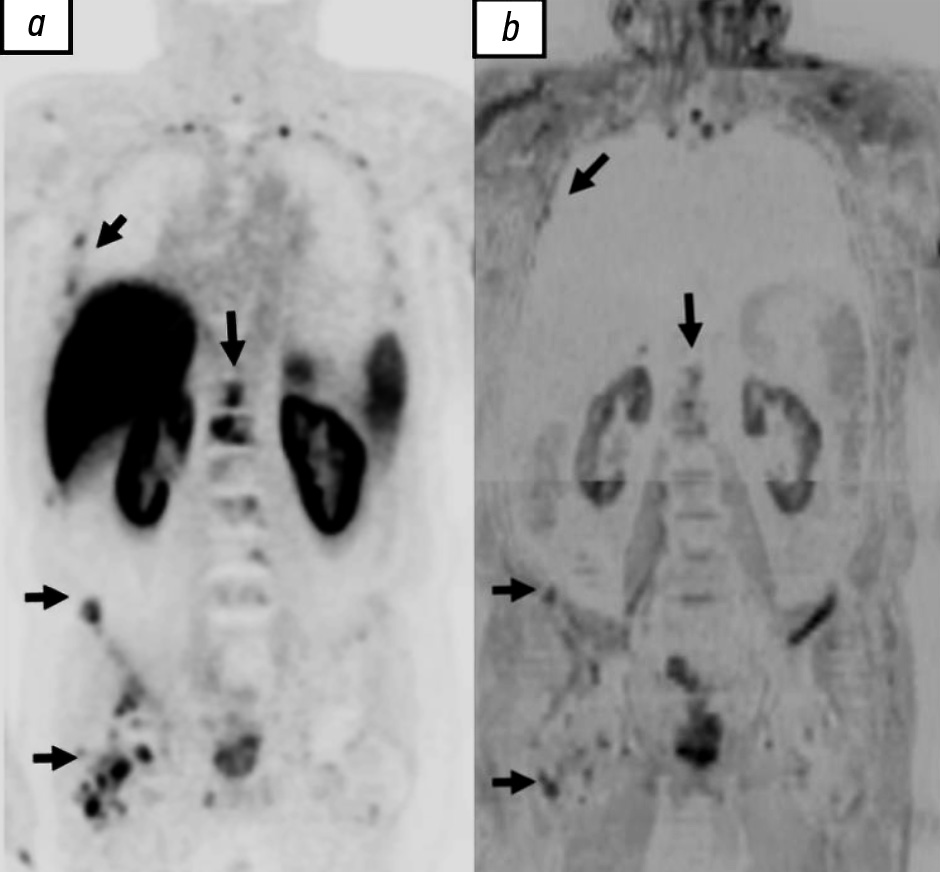

мпМРТ всего тела подразумевает сочетание анатомических и не менее двух функциональных магнитнорезонансных импульсных последовательностей. Протокол сканирования традиционно включает в себя импульсную последовательность T1 Dixon — Т1-ВИ, импульсную последовательность STIR (Short tau inversion recovery — инверсия–восстановление спинового эха) — Т2-ВИ, диффузионно-взвешенную последовательность с различными b-факторами, картами измеряемого коэффициента диффузии (ADC) и в некоторых случаях картами фракций жира (FF maps), динамическим контрастированием и магнитно-резонансной спектроскопией. Несмотря на большую чувствительность мпМРТ всего тела в диагностике локального рецидива, костных и висцеральных метастазов по сравнению с диффузионно-взвешенной, сохраняются трудности при её использовании в отношении выявления метастатического поражения лимфатических узлов (рис. 2) [49, 50].

Рис. 2. Множественные метастазы в костях у пациента с аденокарциномой предстательной железы (Глисон 3+4), собственное наблюдение: a — позитронно-эмиссионная томография с 18F-простатоспецифичным мембранным антигеном-1007; b — инвертированное диффузно-взвешенное изображение всего тела.